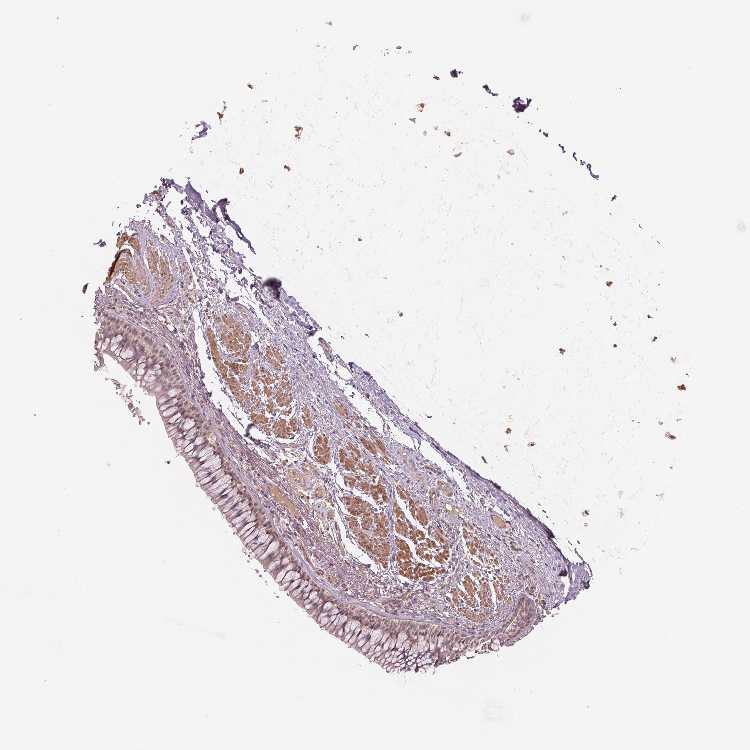

Adipose tissue